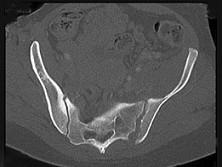

男,56岁,右髋部疼痛,结合图像,最可能的诊断是 ( )A、骨转移瘤B、类风湿关节炎C、骶髂关节结核D、强直性脊柱炎E、骶髂关节炎

问题 男,56岁,右髋部疼痛,结合图像,最可能的诊断是 ( )

选项 A、骨转移瘤 B、类风湿关节炎 C、骶髂关节结核 D、强直性脊柱炎 E、骶髂关节炎

答案 E